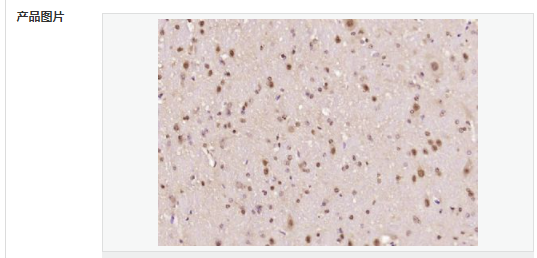

細(xì)胞定位細(xì)胞核 細(xì)胞漿

產(chǎn)品介紹The human ataxin-7 gene, also known as spinocerebellar ataxia 7 or SCA7, maps to chromosome 3p13-p12, has a 2,727-bp open reading frame, and encodes a 892 amino acid protein containing a nuclear localization signal and a polyglutamine tract (1,2). SCA7 is an autosomal dominant neurodegenerative disorder characterized by ataxia and selective neuronal cell loss caused by the expansion of a translated CAG repeat encoding a polyglutamine tract in ataxin-7, which is the SCA7 gene product (3,4). Ataxin-7 is expressed within neurons both affected and unaffected in SCA7 pathology with subcellular localization being variable depending upon the neuronal subtype (5). Polyglutamine expanded in ataxin-7 may carry out its pathogenic effects in the nucleus by altering the matrix-associated nuclear structure and/or by disrupting nucleolar function (6).

Ataxin 7 is a protein of unknown function. It may be the human orthologue of the yeast SAGA SGF73 subunit and a subunit of the human TFTC-like transcriptional complexes. Spinocerebellar ataxia 7 (one of a group of hereditary neurodegenrative diseases) is caused by an expanded trinucleotide repeat in the gene encoding ataxin 7. Ataxin 7 is typically located in the cytoplasm and on the nuclear membrane of normal brain neurons. In cells where there is a mutation of the SCA7 gene, ataxin 7 accumulates in intranuclear inclusions and can result in cell death.